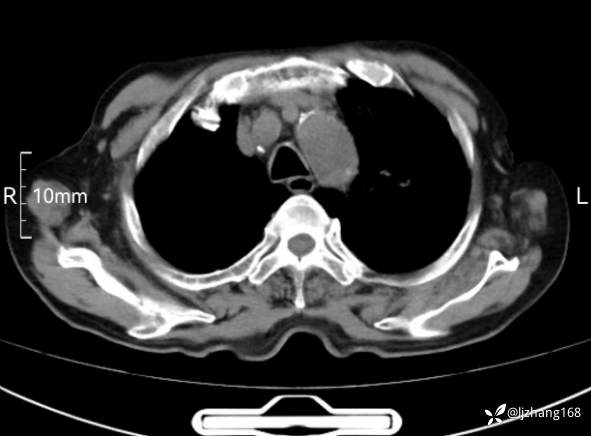

辅助检查:胸部CT:双肺肺气肿,间质性病变,血气分析:PH 7.413, PCO2 29.2mmHg, PO2,81.8mmHg,乳酸 3.3mmol/1,剩余碱-4.0mmol/1,HC03 18.8mmol/1。全血超敏C反应蛋白:超敏C反应蛋白 135.60 mg/L、 白细胞 14x19^9/L,中性粒细胞11.6x10^9/L。